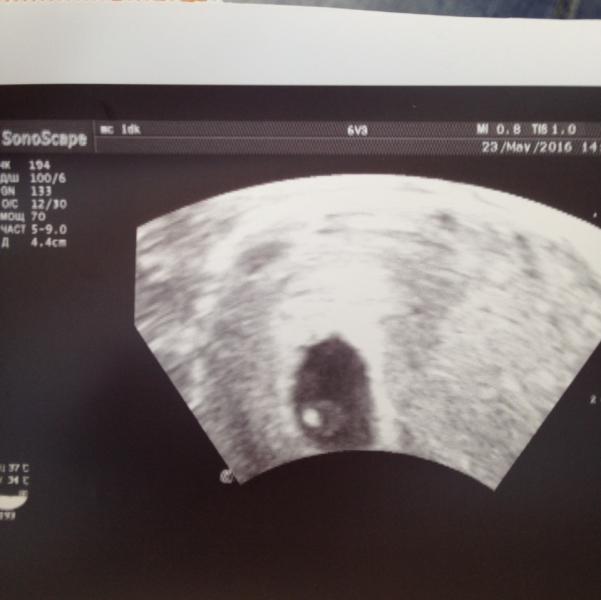

Теперь официально: я буду мамой! Я так боялась! Когда делали УЗИ, врач сказала, что беременность маточная, а я такая: "А она есть?.." =) У моего ребятенка бьется сердечко, там уже видно, что-то трепещет... Я расплакалась прямо на кресле =)